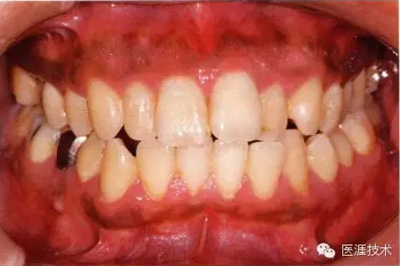

22歲男性牙齦炎的臨床圖像

22歲男性,抽煙(1天約15根,煙齡5年)。刷牙狀態(tài)不佳。抽煙者特有的纖維性牙齦,未見發(fā)紅、腫脹。探針觸診,所有部位均出血。X線牙片未見骨吸收,診斷為牙齦炎。